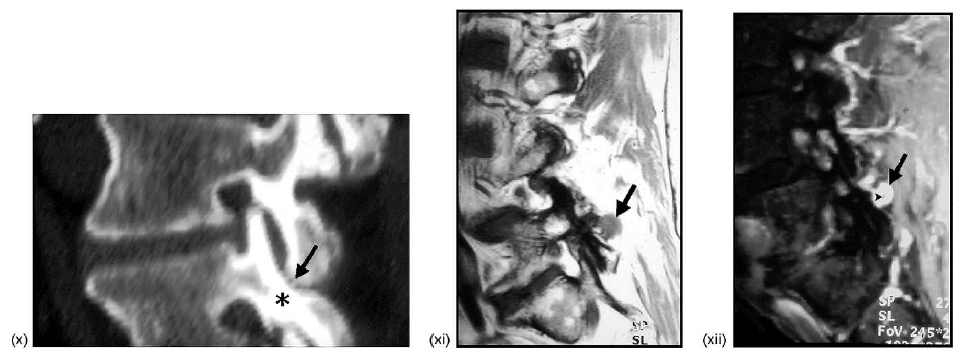

(x) Parasagittal CT reconstruction showing the collision of the tip of the inferior articular facet process of L4 (arrow) with the posterior–superior aspect of the subjacent pars articularis of L5 (asterisk) (compare with (B)).

(xi) Parasagittal T1-weighted MRI showing a posterior neocyst (arrow: i.e., synovial cyst) extending posteriorly from the inferior aspect of the zygapophyseal joint at L4-L5 (compare with (E)).

(xii) Parasagittal T1-weighted fat-suppressed, IV gadolinium-enhanced MRI showing enhancement of the thickened rim of the posterior neocyst (arrow); note the small non-enhancing central area of the cyst (arrowhead; compare with (E)).